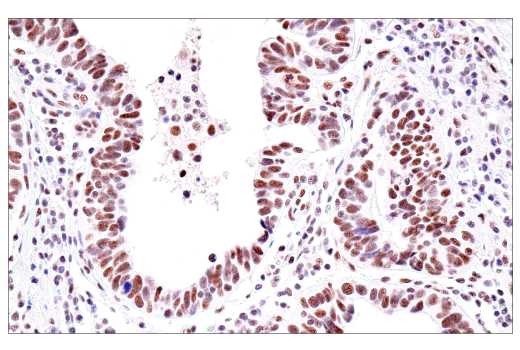

Immunohistochemical analysis of paraffin-embedded human prostate carcinoma using USP39 (E8U2M) Rabbit mAb.

Immunohistochemistry Image 1: USP39 (E8U2M) Rabbit Monoclonal Antibody